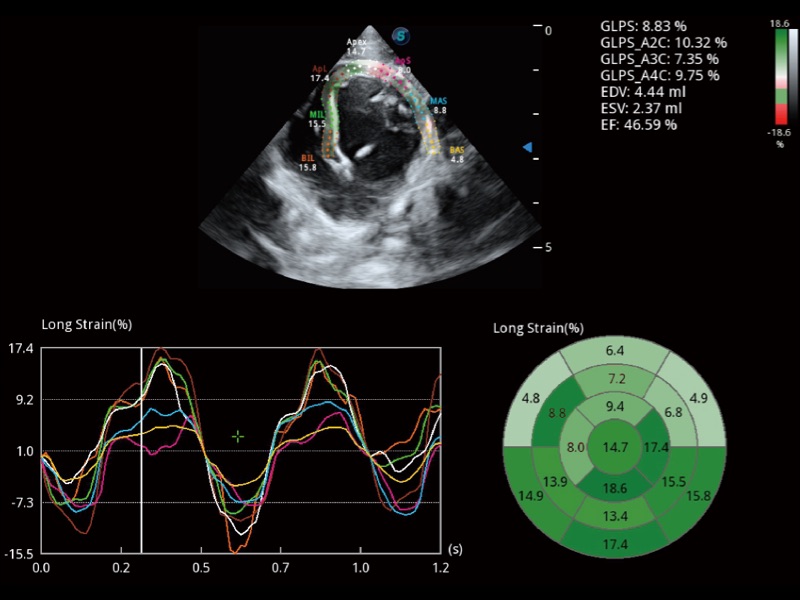

能够基于左心室壁追踪和辛普森法,自动计算射血分数,支持多个可移动点描迹,与手动测量相比,极大节省了动物医生的时间和精力。

通过360度任意调节3条M型取样线,在同一心动周期上观察心脏不同位置的运动曲线,得到准确的心功能测量数据,有效评估心肌运动及左心室功能。

实时用颜色表示心肌组织运动,观察和定量组织的运动情况,对快速检测与评估心肌的灌注和活性、电传导及心肌收缩和舒张功能等均能提供重要的诊断信息。

当心脏测量结果超出正常范围时,可实时预警提示动物医生,减少疾病漏诊概率。